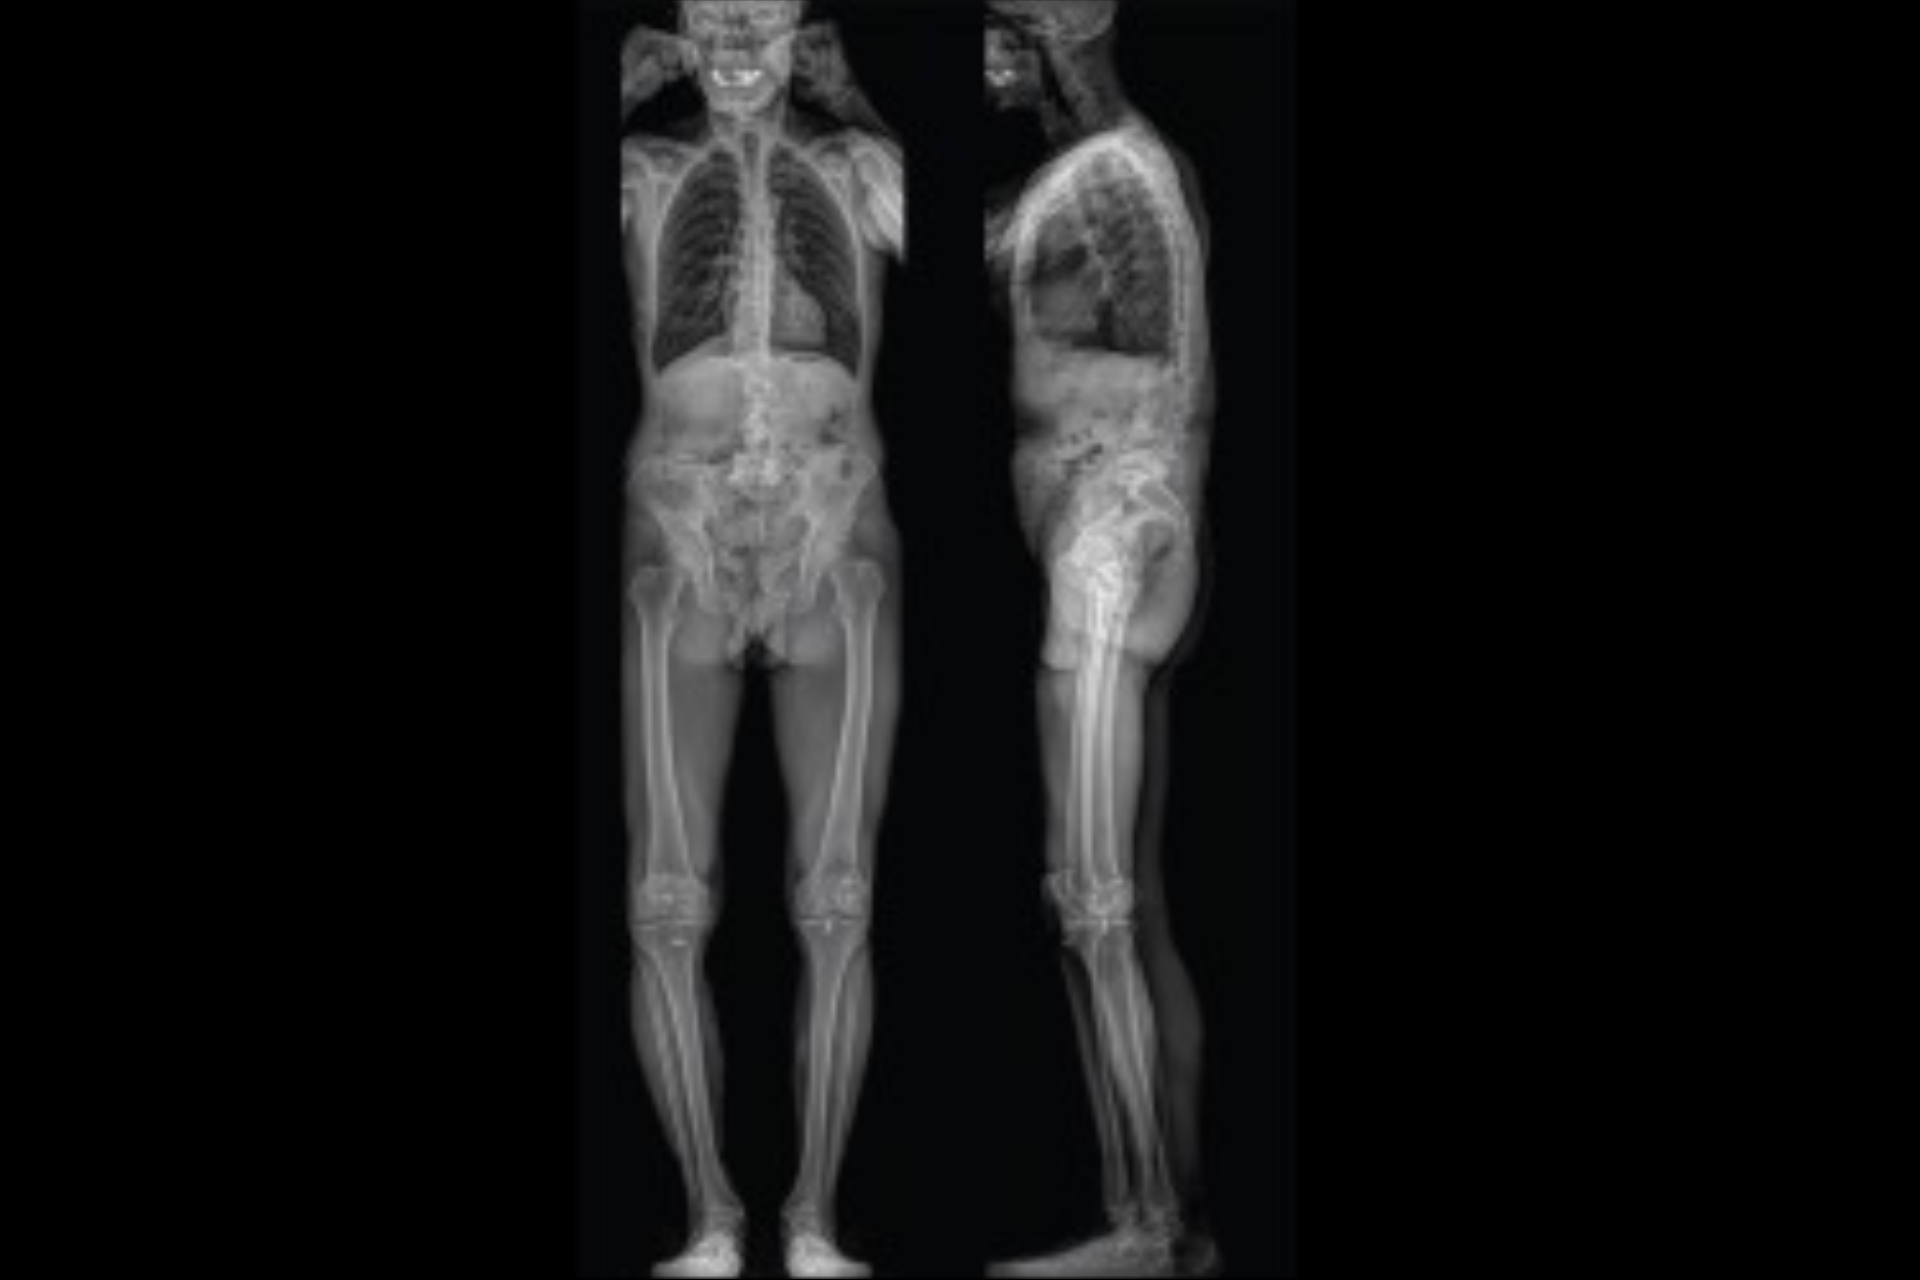

EOS

L’examen EOS est une technique d’imagerie médicale de face et de profil, réalisée en position debout, qui permet d’obtenir une visualisation globale du squelette à faible dose d’irradiation. Cette technologie est particulièrement adaptée à l’étude de l...